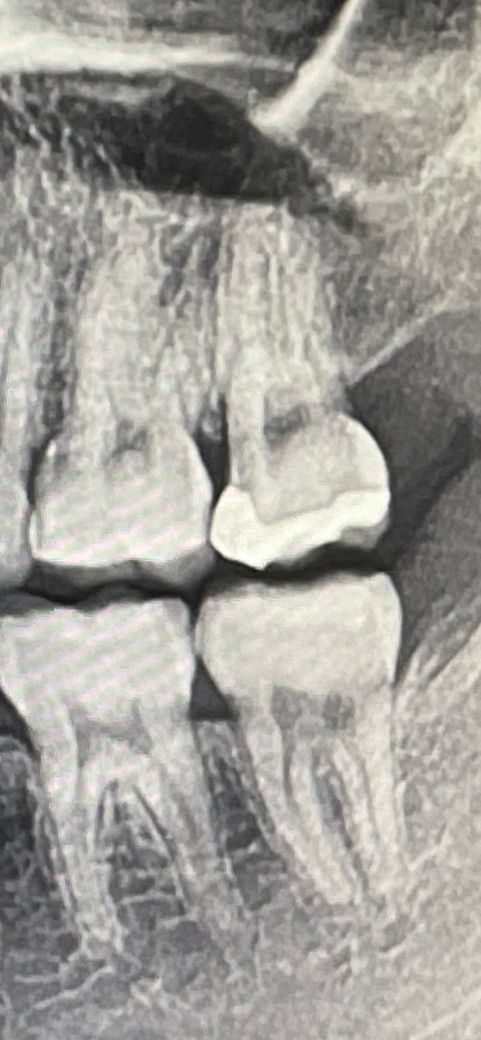

엑스레이 사진상에 충치가 있는지 봐주세요

이 사진은 3주 전에 반대쪽 치아 충치치료 때문에 찍은 사진인데요… 반대쪽 치아 충치 치료 후에 사진에 있는 부분이 어쩌다 한 번 시릴 때가 있어요

기분탓인지 충치가 생겼는지 모르겠네요.. 지난번 치과치료에서 사진 부분에선 충치 이야기를 안 하셨는데 못보신건지 없는건지…

충치가 의심되는건 사진상에 위쪽 가장뒤 치아가 치료한 곳 아래부위에 충치가 생긴거 같습니다.

사진상으로는 충치가 보이진 않아 보입니다. 하지만 충치의 여부는 육안으로도 확인을 해야 할 수 있습니다.

충치가 의심되는 부분은 있으나 파노라마 엑스레이 사진은 화질이 떨어져서 정확한 판독은 어렵습니다. 치근단사진(작은 엑스레이사진)을 찍어봐야 합니다.

치아에 충치가 있어보이진 않습니다. 2차우식이 의심되는 곳도 있으나 이는 엑스레이를 정기적으로 찍어 검사해야합니다.

사진만 봤을때는 확실히 충치가 있다라고 보이는 곳은 없습니다. 치경부 소환이라고 해서 치아의 목부위가 다른 곳들에 비해 방사선 투과상(검게 보이는)으로 보이기도 하는데요. 사진상에서 치경부 소환이

어느정도 관찰되긴 하지만 충치라고 보기엔 좀 힘듭니다.